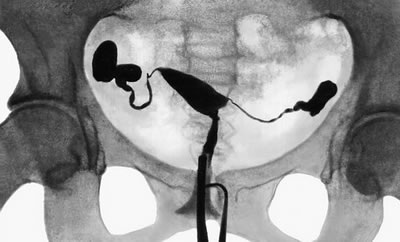

Трубный фактор – это чуть ли не основополагающая причина бесплодия у женщин. В клинической практике он встречается часто. Порой, девушки даже не думают о том, чтобы лечить инфекционные заболевания. Они не думают о последствиях своих действий, а точнее сказать бездействий. Лишь тогда, когда они начинают планировать беременности, они вспоминают прежние проблемы.Маточные трубы Они считаются парным органом. Их основная функция заключается в том, чтобы транспортировать оплодотворенную яйцеклетку в маточную полость. Оплодотворение зрелой яйцеклетки сперматозоидами происходит именно в них. Реснички эпителия отвечают за перемещение оплодотворенной яйцеклетки. Эти реснички выстилают просвет трубы. Если просвет будет блокирован из-за спаек или воспалительной жидкости, то у женщины могут диагностировать бесплодие. Оно развивается на фоне того, что сперматозоид и яйцеклетка не могут встретиться друг с другом. Почему может развиться трубное бесплодие? Врачи-гинекологи говорят, что причин, которые влияют на изменение строения и функции маточных труб, очень много. Как правило, бесплодие развивается на фоне воспалительных болезней, эндометриоз, оперативные вмешательства. Оно может развиться на фоне острых и хронических воспалительных заболеваний органов малого таза. Микроорганизмы с патогенной природой могут поразить эпителий труб матки. Спайки появляются из-за гонококков и хламидий. Они-то и закрывают просвет в трубах, формируя пиосальпинксы, гидросальпинксы, сактосальпинксы. Если трубы существуют в таком виде долго, эпителий гибнет. Даже если провести оперативное вмешательство, вылечить этот вид бесплодия практически невозможно. Воспаление играет второстепенную роль, а вот на первый план выходит наружный генитальный эндометриоз. Если он поразит трубы, то они станут непроходимыми. Также происходит спаечный процесс в малом тазу, из-за этого изменяется расположение яичников, маточных труб. Что еще может привести к трубному бесплодию? Удаление аппендицита сопровождается воспалительным процессом, который может также привести к спайкам. Как определить «проходимость»? Итак, супружеская пара обращается в клинику за помощью. Им назначают диагностические процедуры, которые помогут выявить «проходимость» маточных труб и активность сперматозоидов. Эти исследования основные и первостепенные, и не надо отказываться от них. Врач вправе назначить лапароскопию, гидросонографию, гистеросальпингографию. Есть ли способ вылечиться? Лапароскопия – это не только самая эффективная методика определения «непроходимости» труб, но и основополагающий метод лечения. Обратившись к ней, можно провести интраоперационное контрастирование труб. Врач может разделить имеющиеся спайки, чтобы восстановить проходимость и добиться правильного взаимоотношения с другими органами малого таза. |